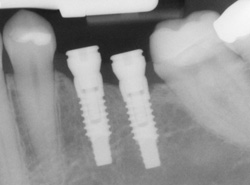

- Computer-Enhanced Treatment Planning: We have special software on our computer that allows us to evaluate your dental CT scan in three dimensions for bone quality, bone quantity, and bone location, enabling the best possible placement of your dental implants. This also allows us to work closely and smoothly with your restorative dentist to ensure an ideal result where your dental implants are concerned.